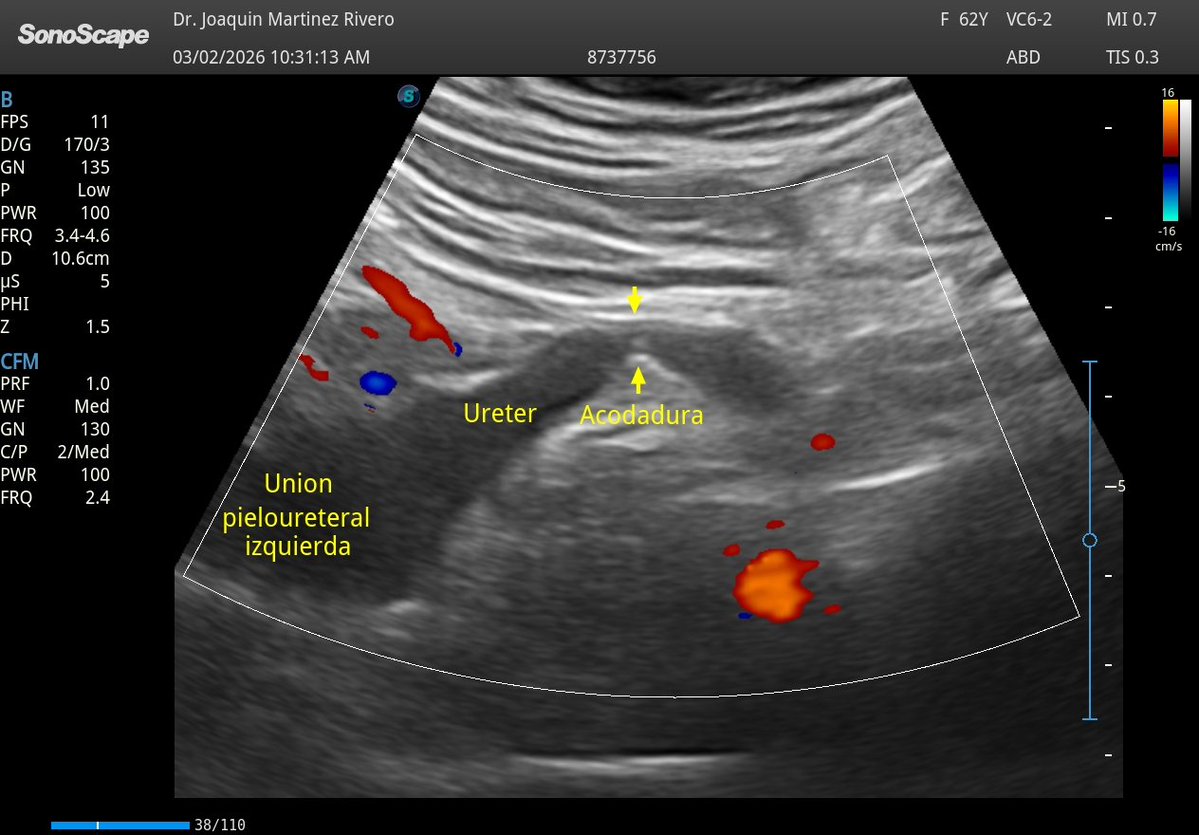

Acodadura ureteral izquierda. Confirmación con CT.

@javiteigell @NephroP @OswaldoRamosN @PierpaDiNick @y_interna @yaletung @SonoSamMD @curromir @zbriote @ABCDEcografia @AlvarezHigueras @ignaciomsb @jpalacinp @EcosemfyC @USPed_Latam @GTEcoPed @GTECOSEMI Sí, acá el 3D le hizo justicia al caso. 🙏🏻🙏🏻🙏🏻🙏🏻🙏🏻

Español

@JMMR83 @NephroP @OswaldoRamosN @PierpaDiNick @y_interna @yaletung @SonoSamMD @curromir @zbriote @ABCDEcografia @AlvarezHigueras @ignaciomsb @jpalacinp @EcosemfyC @USPed_Latam @GTEcoPed @GTECOSEMI Qué bien se ve este!!